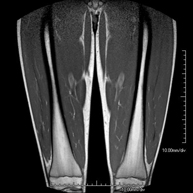

Exploració ideal per estudiar les lesions en músculs isquiotibials i quàdriceps, sovint lesionats en esportistes. També permet una bona valoració de tendons i de nervis perifèrics. La durada aproximada és de 20 minuts. No utilitza radiació ionitzan. - RM de Genoll

Exploració per estudiar lesions a l'articulació, com trencaments dels meniscals i dels lligaments creuats (únicament es poden detectar amb aquesta prova), condropatia o desgast del cartílag i moltes altres alteracions derivades de l'activitat esportiva i dels canvis degeneratius (osteoartrosi). La durada aproximada és de 18 minuts. No utilitza radiació ionitzant. - RM de Cama

Exploració per estudiar lesions a tendons, a músculs i a nervis perifèrics. És de gran utilitat per diagnosticar ruptures fibrilars als bessons. La durada aproximada és de 18 minuts. No utilitza radiació ionitzant. - RM de Turmell